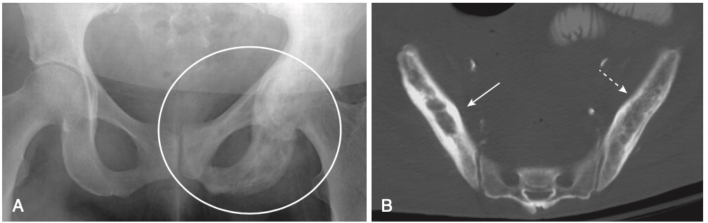

- Một chất được tiết từ các tế bào u của ung thư biểu mô tuyến tiền liệt có thể kích thích hoạt động của tạo cốt bào và tạo ra các vùng tăng đậm độ xương khu trú. Những tổn thương này thường thấy nhất ở đốt sống, xương sườn, xương chậu, xương đùi và xương đùi (Hình-5).

- Trên phim X quang thông thường, vùng hoại tử vô mạch xuất hiện đậm đặc hơn vùng xương xung quanh. Trên MRI, thường có sự giảm tín hiệu so với bình thường (cao) do tủy mỡ (Hình-6).

- Phần xương bị mất mạch máu trở nên đặc hơn và do đó có vẻ xơ cứng hơn phần xương còn lại. Điều này thấy rõ ở chỏm xương đùi (Hình-7) và chỏm xương cánh tay.